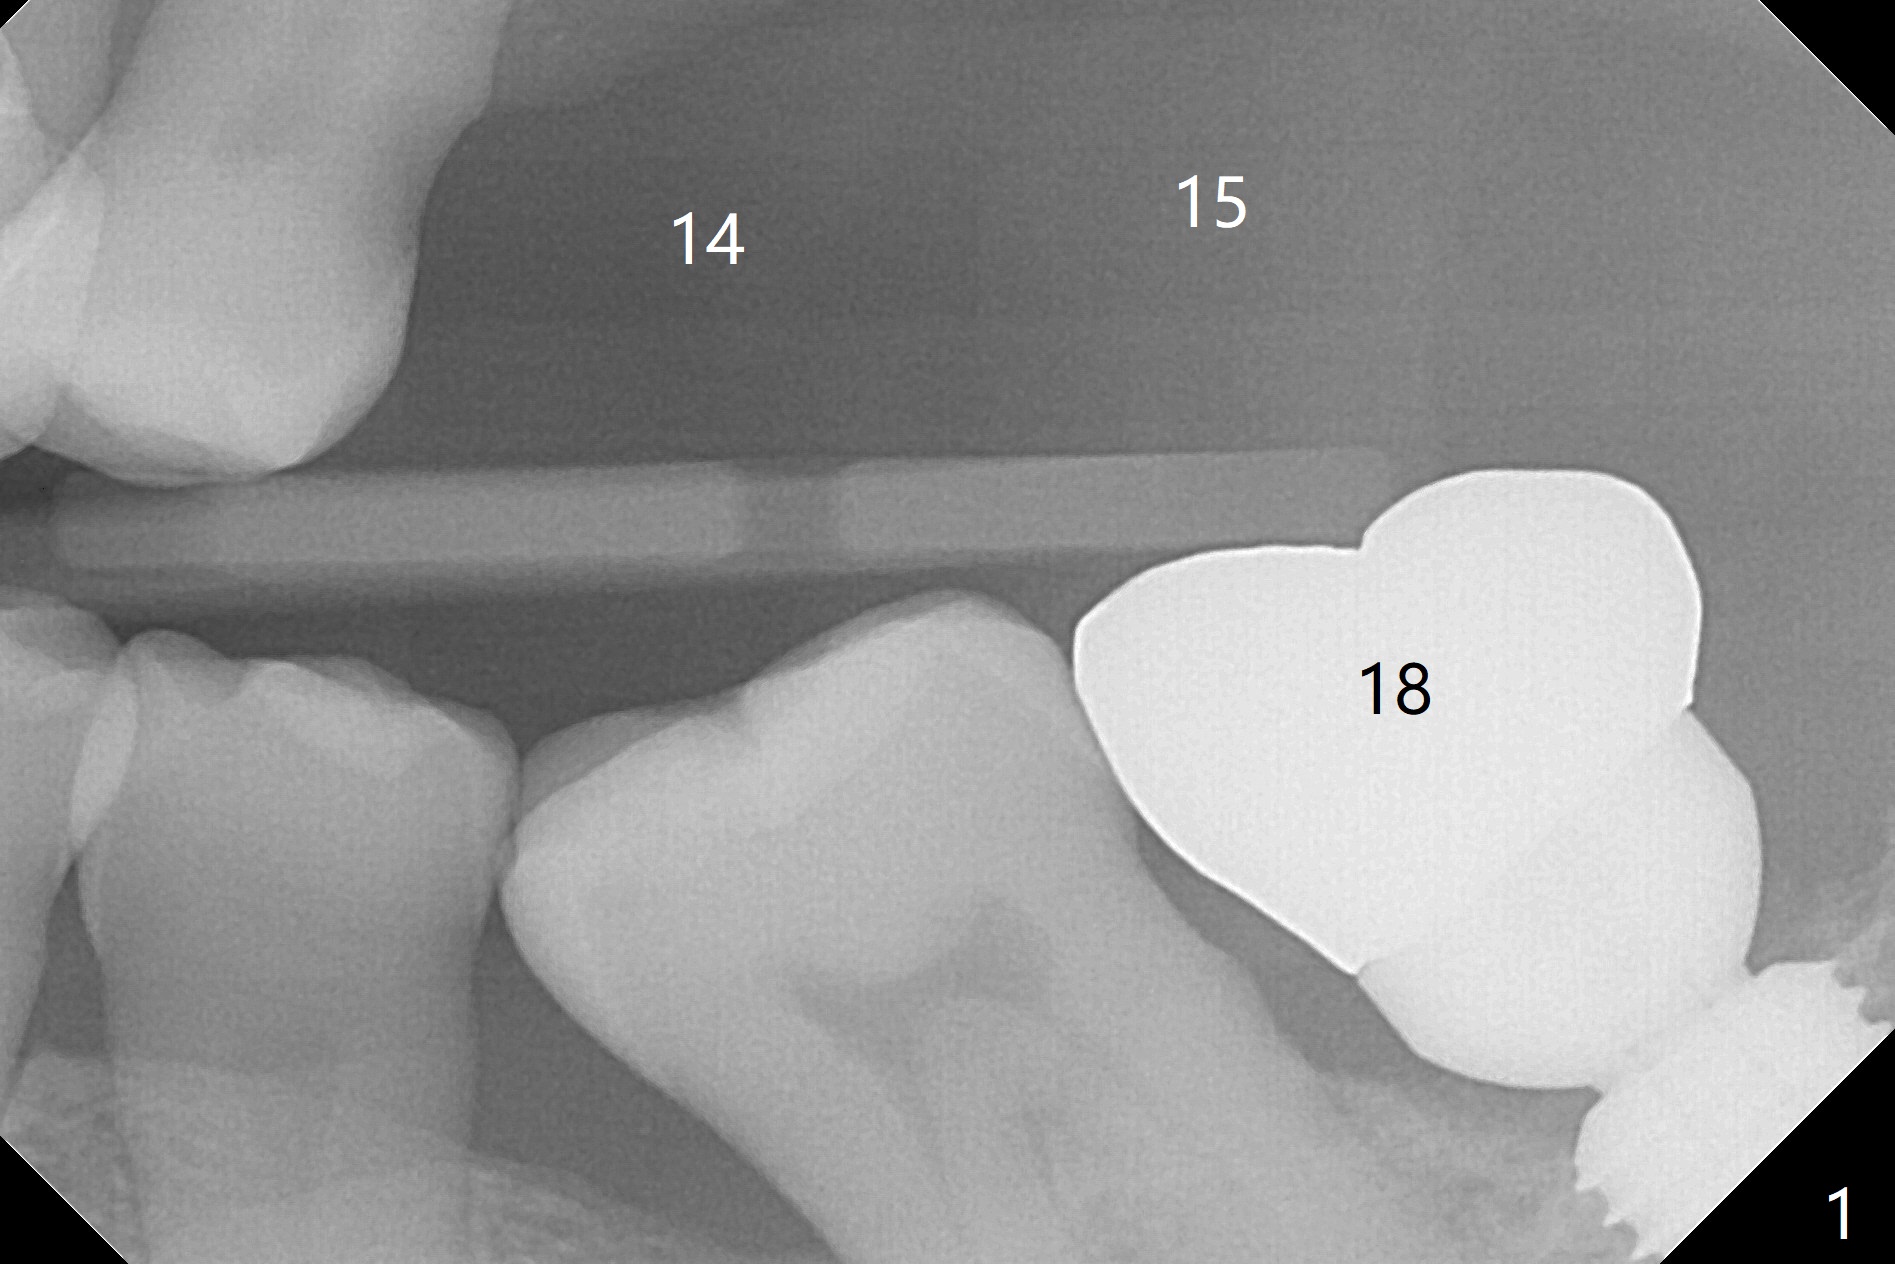

A 66-year-old man with 4 implants in function returns requesting one more at the upper left sextant (Fig.1).  With the opposing implant at #18, two implants at #14 and 15 are necessary.  Can guided surgery be performed with sinus lift (Fig.2)?

With CT, it appears that 5x8.5 and 10 mm implants are to be placed without and with simultaneous sinus lift (Fig.3).  Take photos of the teeth with gingival erythema, as compared to the implants placed.